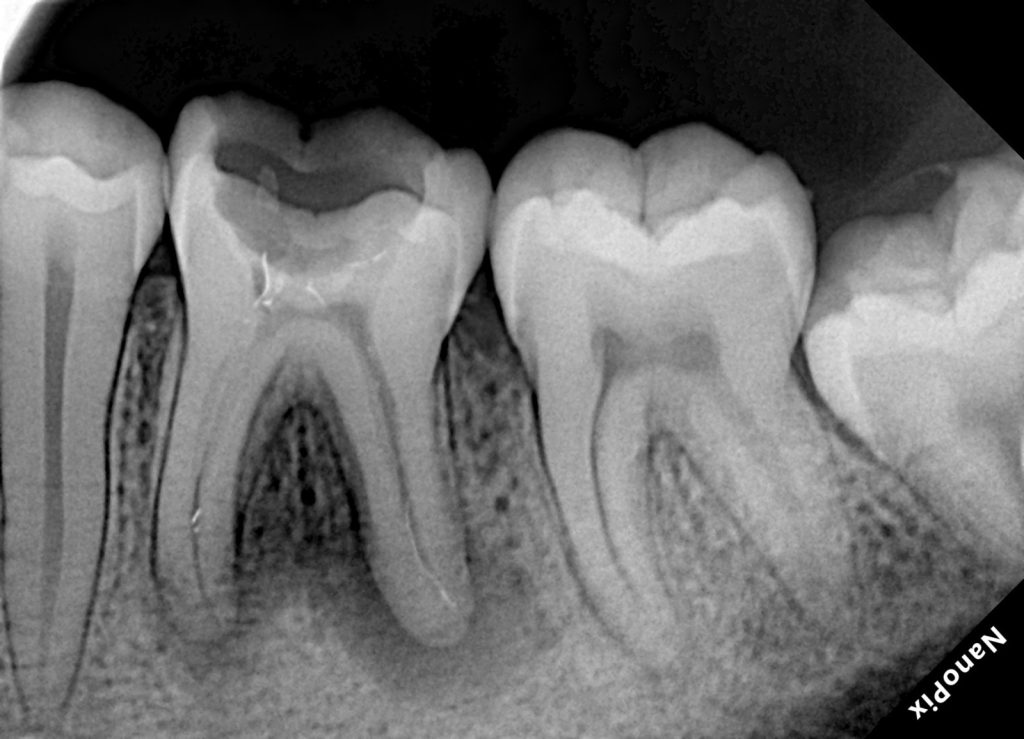

Diagnosis and Treatment Planning

Clinical examination revealed a deeply carious mandibular first molar associated with pulpal pathology. Percussion sensitivity and radiographic findings confirmed the need for root canal treatment. The tooth exhibited weakened cusps due to caries and access requirements.

Conservative access preparation was performed with attention to maintaining pericervical dentin. The canal system was identified and negotiated systematically. Working lengths were established, and patency was confirmed.

Cleaning and shaping were carried out using a controlled, biologically respectful approach, ensuring adequate irrigation and disinfection while preserving canal anatomy.

Obturation

Following complete drying of the canals, obturation was performed to achieve a dense, three-dimensional seal. Special care was taken to ensure proper adaptation in the apical and coronal thirds.

A definitive coronal seal was placed immediately after obturation to prevent microleakage.